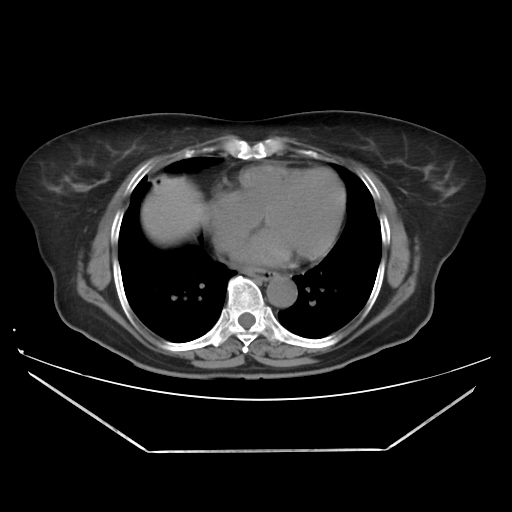

A CT abdomen revealed a left adrenal cortical tumor.

CT images: